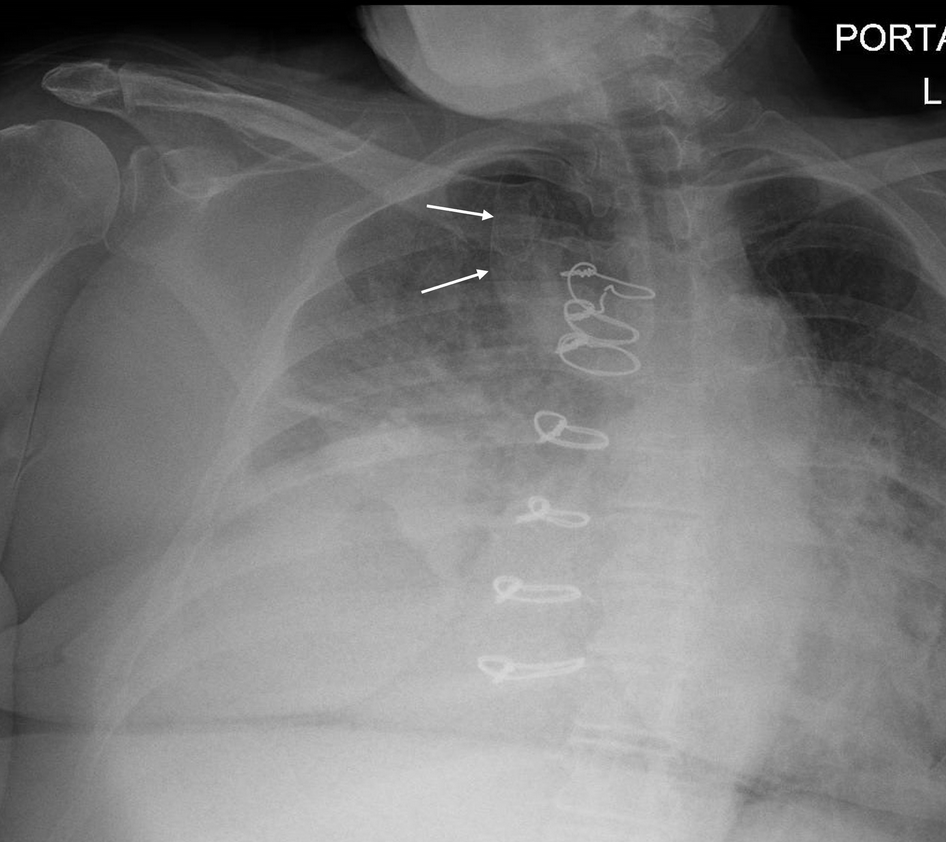

Normal anatomic variation is important for the intensivist to recognize so that findings are not confused for pathology. This chest radiograph shows an azygos fissure—the most common accessory fissure, present in roughly 0.5% of patients. The azygos fissure and lobe form during embryology, when the posterior cardinal vein (precursor of a segment of the azygos vein) aberrantly migrates through the upper lobe. As a result, two layers of pleura are carried through the lobe to produce the azygos fissure. This can be confused with abscess, bulla, or pneumothorax. The structure is even more readily evident on CT scanning (Figure 2). An azygos lobe is not a true lobe because it lacks a bronchus. There is no medical significance to an azygos fissure, but it does require awareness by an operating surgeon.

Retained guidewires are common but are more radiopaque than the finding seen here. Pneumothorax will generally not leave evident lung distal to the pleural line, as is seen here. Moreover, the location on this chest radiograph is typical of an azygos lobe. Colonic and gastric interposition used in treatment of esophageal cancer can produce confusing shadows on a chest radiograph, but the appearance here is not typical.234